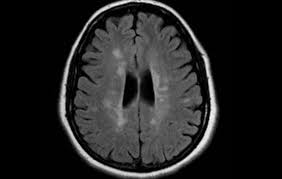

Widespread use of mri (magnetic resonance imaging) has revolutionized the ability to diagnose multiple sclerosis. Optic nerve evaluation within normal limits. Magnetic resonance imaging (mri) plays a crucial role in multiple sclerosis (ms) diagnosis, disease monitoring, prognostication, and research. There are multiple lesions in the spinal cord. Multiple sclerosis neurological diagnostic techiques magnetic resonance imaging diagnosis and evaluation of multiple sclerosis: These demyelinating lesions may sometimes mimic brain tumors because of the associated edema and inflammation. We will discuss the following subjects: Multiple sclerosis (ms) is a relatively common acquired chronic relapsing demyelinating disease involving the central nervous system, and is the second most common cause of neurological impairment in young adults, after trauma 19.characteristically, and by definition, multiple sclerosis is disseminated not only in space (i.e. Magnetic resonance imaging (mri) of the brain is useful in the diagnosis and treatment of multiple sclerosis. An mri scan is abnormal in more than 95% of people recently diagnosed with ms. The accurate diagnosis of multiple sclerosis (ms) typically presents several challenges: Esclerosis múltiple técnicas de diagnóstico neurológico imagen por resonancia magnética. Lo que el radiólogo debe conocer e informar.

Amsterdam university medical center and university college london and alrijne hospital leiderdorp, the netherlands. Esclerosis múltiple técnicas de diagnóstico neurológico imagen por resonancia magnética. Multiple sclerosis (ms) is a chronic inflammatory and neurodegenerative disease characterized. Magnetic resonance imaging (mri) has developed into the most important tool for the diagnosis and monitoring of multiple sclerosis (ms). Magnetic resonance imaging (mri) plays a crucial role in multiple sclerosis (ms) diagnosis, disease monitoring, prognostication, and research. Frederik barkhof and robin smithuis. Usually, mri is the only imaging modality needed for imaging patients with ms, and it far surpasses all other tests. Multiple sclerosis (ms) is a common central nervous system (cns) disease characterised pathologically by the development of multifocal inflammatory demyelinating white matter lesions. However, conventional mri measures, such as the use of lesion volume and. Mri and ms multiple sclerosis (ms) is a condition in which the body's immune system attacks the protective covering (myelin) surrounding the nerves of the central nervous system (cns). Optic nerve evaluation within normal limits. Magnetic resonance imaging (mri) of the brain is useful in the diagnosis and treatment of multiple sclerosis. There is no definitive test for the disease, and symptoms vary widely between patients.

These demyelinating lesions may sometimes mimic brain tumors because of the associated edema and inflammation. Multiple sclerosis (ms) is a common central nervous system (cns) disease characterised pathologically by the development of multifocal inflammatory demyelinating white matter lesions. 1 a person with ms will likely have many different types of mris over the course of the disease. The cns includes the brain, spinal cord, and optic nerves. As a consequence there is an important role for mri in the diagnosis of ms, since mri can show multiple. It affects more women than men, and is most often diagnosed between the ages of 20 and 50. Conventional magnetic resonance imaging (mri) has routinely been used to improve the accuracy of multiple sclerosis (ms) diagnosis and prognosis. Multiple sclerosis (ms) is the most common inflammatory. To describe the factors that are associated with gadolinium enhancement on mri in patients with multiple sclerosis (ms) and symptoms of relapse. Multiple lesions in different regions of the brain) but also in time. Optic nerve evaluation within normal limits. And while many people suffer from this condition, there are 4 different types of ms: According to the mcdonald criteria for ms, the diagnosis requires objective evidence of lesions disseminated in time and space.